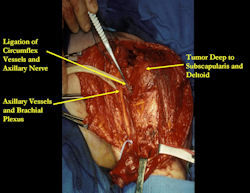

Examples of radical limb sparing surgeries for osteosarcomas in various anatomic locations (distal femur, proximal tibia, proximal humerus, scapula)

In each case, the tumor and bone from which it arose were resected. This required meticulous dissection, mobilization and preservation of adjacent pertinent neurovascular structures. In each case presented here, the defect was reconstructed with a special modular segmental tumor prosthesis. This also replaces the adjacent joint in many instances.

Proximal Humerus: Radical Limb Sparing Extra-Articular Resection and Prosethetic Reconstruction